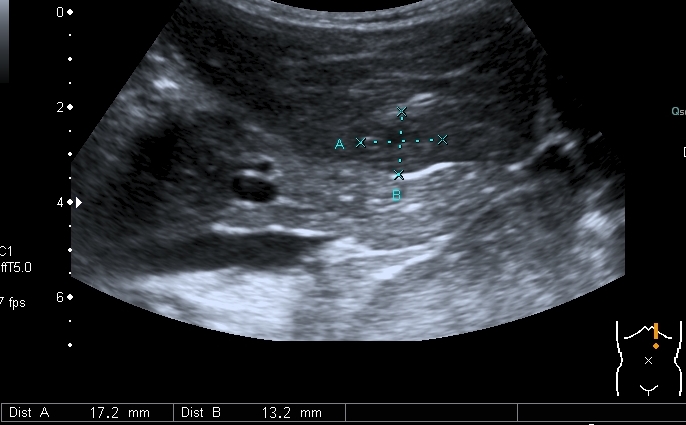

Добавляю сканы печени, я думаю они являются хорошей подсказкой о природе изменений в лёгких

Правая доля печени

Она же  с  высокочастотным датчиком субкапсулярно